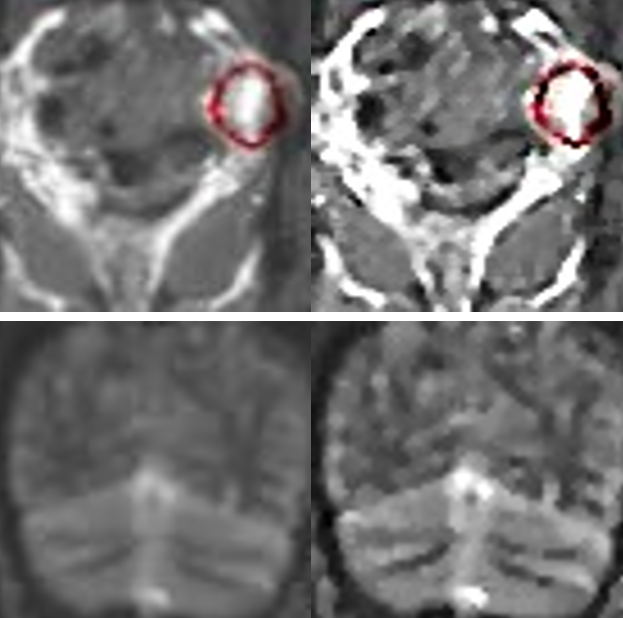

From the overall and detailed enhancement effects in Figure 3, it can be observed that the image enhancement method proposed in this paper effectively highlights the MRI texture details, providing quality assurance support for target detection.

(a) (b)

Figure 3. Comparison of Image Enhancement Effects. (a) Overall comparison; (b) Detailed comparison.